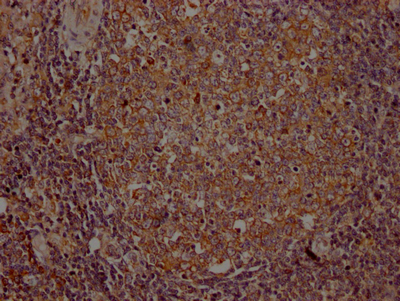

• IHC image of CSB-RA954682A0HU diluted at 1:100 and staining in paraffin-embedded human lymph node tissue performed on a Leica BondTM system. After dewaxing and hydration, antigen retrieval was mediated by high pressure in a citrate buffer (pH 6.0). Section was blocked with 10% normal goat serum 30min at RT. Then primary antibody (1% BSA) was incubated at 4℃ overnight. The primary is detected by a Goat anti-rabbit IgG polymer labeled by HRP and visualized using 0.05% DAB.